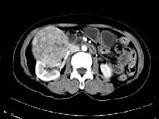

女,57岁,右腰部胀痛6月余,触及右侧腹部包块2月,CT平扫及增强如图所示,下列说法正确的是?(?)

• A.平扫时可见右侧腹部巨大的软组织肿块影,其内可见小片状的低密度影

• B.增强扫描肿块强化明显,其内可见无强化的低密度坏死灶

• C.考虑肿块来源于肝脏,是原发性肝癌,并挤压推移右肾

• D.考虑肿块来源于右肾,是巨大的肾癌,并挤压推移右肝,与其分界欠清

• E.考虑肿块来源于右肾,是肾血管平滑肌脂肪瘤,并挤压推移右肝,与其分界欠清